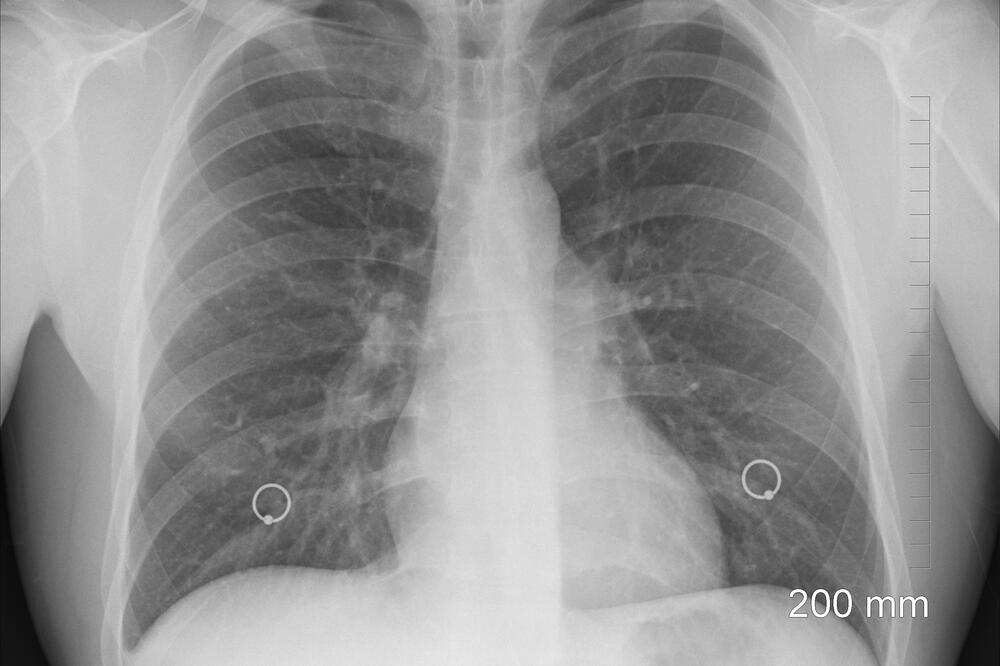

Ilustracija, Foto: Pixabay